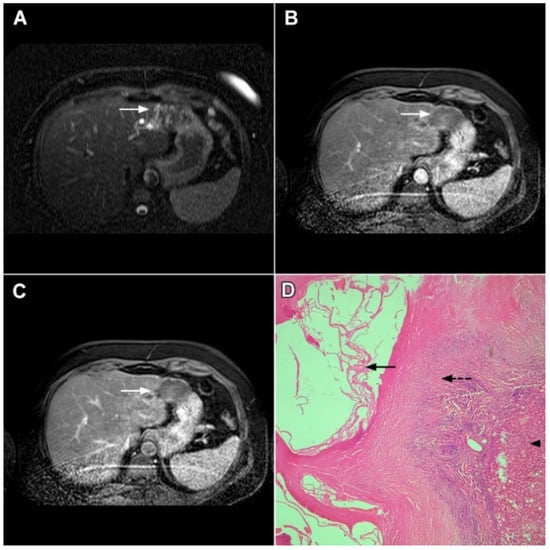

Ancillary MRI findings that are frequently seen in mICC include peripheral biliary dilatation, capsular retraction, vascular encasement, lobar atrophy, satellite nodules, and lymphadenopathy [15,16]. Nevertheless, it should be kept in mind that in the parenchymal type of mICC, due to its origin from the small bile ducts, ancillary features such as biliary dilatation, vascular encasement, and lobar atrophy may be absent (Figure 5). In such cases, the presence of typical postcontrast behavior and capsular retraction indicate mICC. On the other hand, some degree of obstruction and peripheral bile duct dilatation is always seen in the ductal type of mICC [15].

Figure 5.

Parenchymal mass-forming cholangiocarcinoma in a 36-year-old man. The lobular slightly hyperintense lesion (arrow) is seen in the liver segment IVA in a T2-weighted image (A) with subtle capsular retraction (dashed arrow). On a plain T1-weighted image (B), the tumor (arrow) is hypointense with irregular discrete peripheral and central enhancements in the arterial phase (C), mild progressive enhancement in the portal venous phase (D), and high signal intensity in DWI (E). Hematoxylin and eosin (H&E) staining (F) showed cholangiocarcinoma (arrowhead) with poorly differentiated components (dashed arrow). Normal liver parenchyma is also shown (arrow); original magnification ×40.

2.2. Atypical Imaging Features of mICC

Besides the typical imaging presentation of mICC, atypical appearance can also be observed in imaging studies [24]. Hypervascular mICCs are usually small lesions and this vascular behavior might be explained by less intralesional fibrosis and abundant vascular stroma [25]. The incidence of hypervascular mICC ranges from 12.5% up to 47% in previous reports [18,25]. Since hypervascular mICCs are frequently seen in cirrhotic livers, the differential diagnosis with HCC may be very difficult. In this regard, the absence of washout and the presence of progressive enhancement together with the lack of fibrous pseudocapsule favor the diagnosis of mICC over HCC [25]. However, if hypervascular mICC shows washout in the portal venous phase, preoperative differential diagnosis with HCC is hardly possible (Figure 6). In such cases, additional findings, such as cloud appearance in the hepatobiliary phase, multiplicity around the main tumor, or intrahepatic metastasis, capsule retraction and tumor markers may be helpful for differentiating between these tumors [18,19]. Hypervascular mICC differs from typical hypovascular mICC not only in terms of vascularity but also in patient outcome, as it has been shown that the former has much better prognosis [12]. Therefore, the assessment of tumor vascularity on preoperative imaging could represent an important marker for predicting malignant characteristics in mICC [26].

Figure 6.

Hypervascular mass-forming cholangiocarcinoma in a 63-year-old woman. The axial T2-weighted image (A) shows a moderately hyperintense tumor (arrow) located in liver segments VI and VII with a subtle medial capsular retraction. The lesion (arrow) is hypointense on the plain T1-weighted image (B), hypervascular in the arterial phase (C) with washout on the portal venous phase (D). The tumor (arrow) is hyperintense on DWI (E). Hematoxylin and eosin (H&E) staining (F) showed well-differentiated cholangiocarcinoma (arrow) surrounded by normal liver parenchyma (dashed arrow); original magnification ×40.